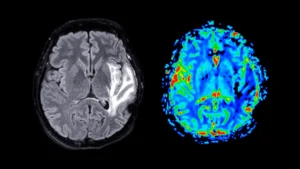

The burgeoning landscape of Alzheimer’s disease therapeutics has recently welcomed a novel class of medications demonstrating the...